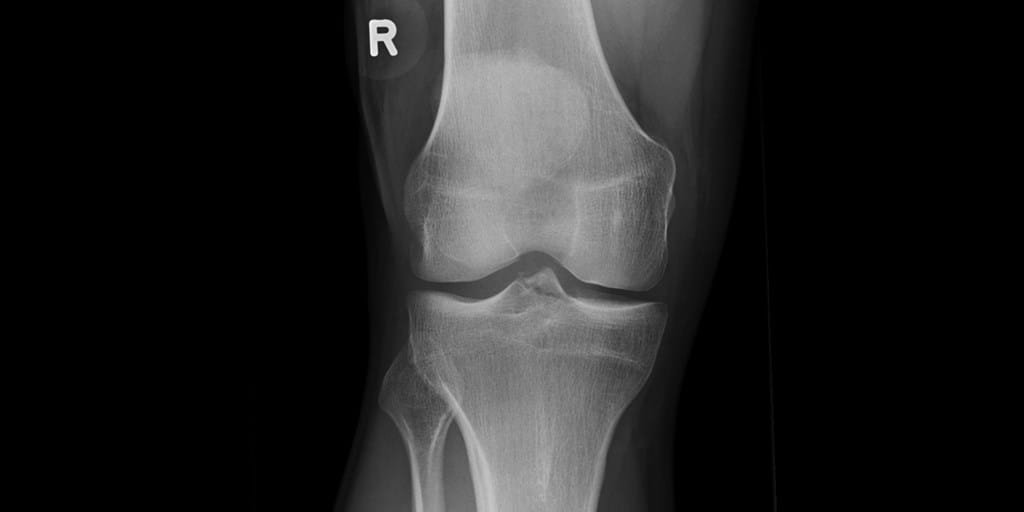

Knee Conditions GET IN TOUCH Knee Arthritis Meniscal Tears ACL Tears Knee Instability The Painful Or Failing Knee Replacement Knee Arthritis Learn MOre Meniscal Tears Learn MOre ACL Tears Learn MOre Knee Instability Learn MOre The Painful Or Failing Knee Replacement Learn MOre KNEE SURGERY OUR SERVICES If joint pain or injury is affecting your daily life, Dr Paterson is here to support your recovery with individualised, evidence-based care. Knee Arthritis Learn MOre Meniscal Tears Learn MOre ACL Tears Learn MOre Knee Instability Learn MOre The Painful Or Failing Knee Replacement Learn MOre OTHER TREATMENT OPTIONS